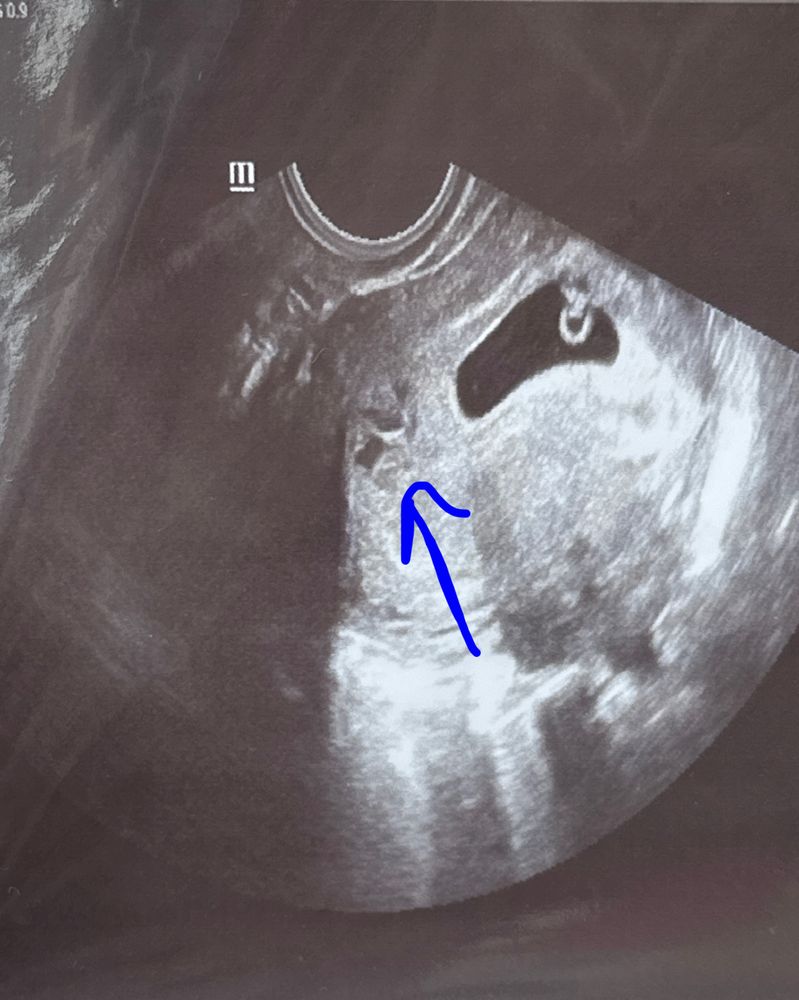

Срок 7 недель. На сроке 4 недели увидела немного крови, в больнице сказали все хорошо, но прописали дюфастон(пью). В 6нед 1д пошла на узи, увидели гематому, но сказали она не свежая и должна выйти. До сих пор никаких выделений нет и иногда тянет низ живота (не сильно). Переживаю( у кого-нибудь она проходила без выделений?

У вас она ещё далеко расположена от ПЯ, так что думаю не должна она как-то влиять на малыша